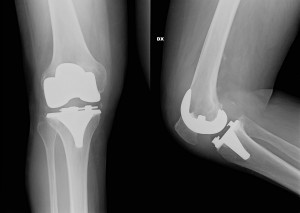

Un’accurata visita specialistica deve sempre essere alla base del sospetto clinico, indirizzando i successivi esami da effettuare. In caso di ulteriori approfondimenti il Medico può richiedere l’esecuzione di una radiografia per una visione globale nelle artrosi e nelle deviazioni assiali, ottenendo un’ottima visione dell’anatomia del segmento osseo. In alcuni casi viene prescritta la Risonanza Magnetica, utile ad esempio per problematiche come patologie meniscali o ligamentose, o per problemi cartilaginei parziali.